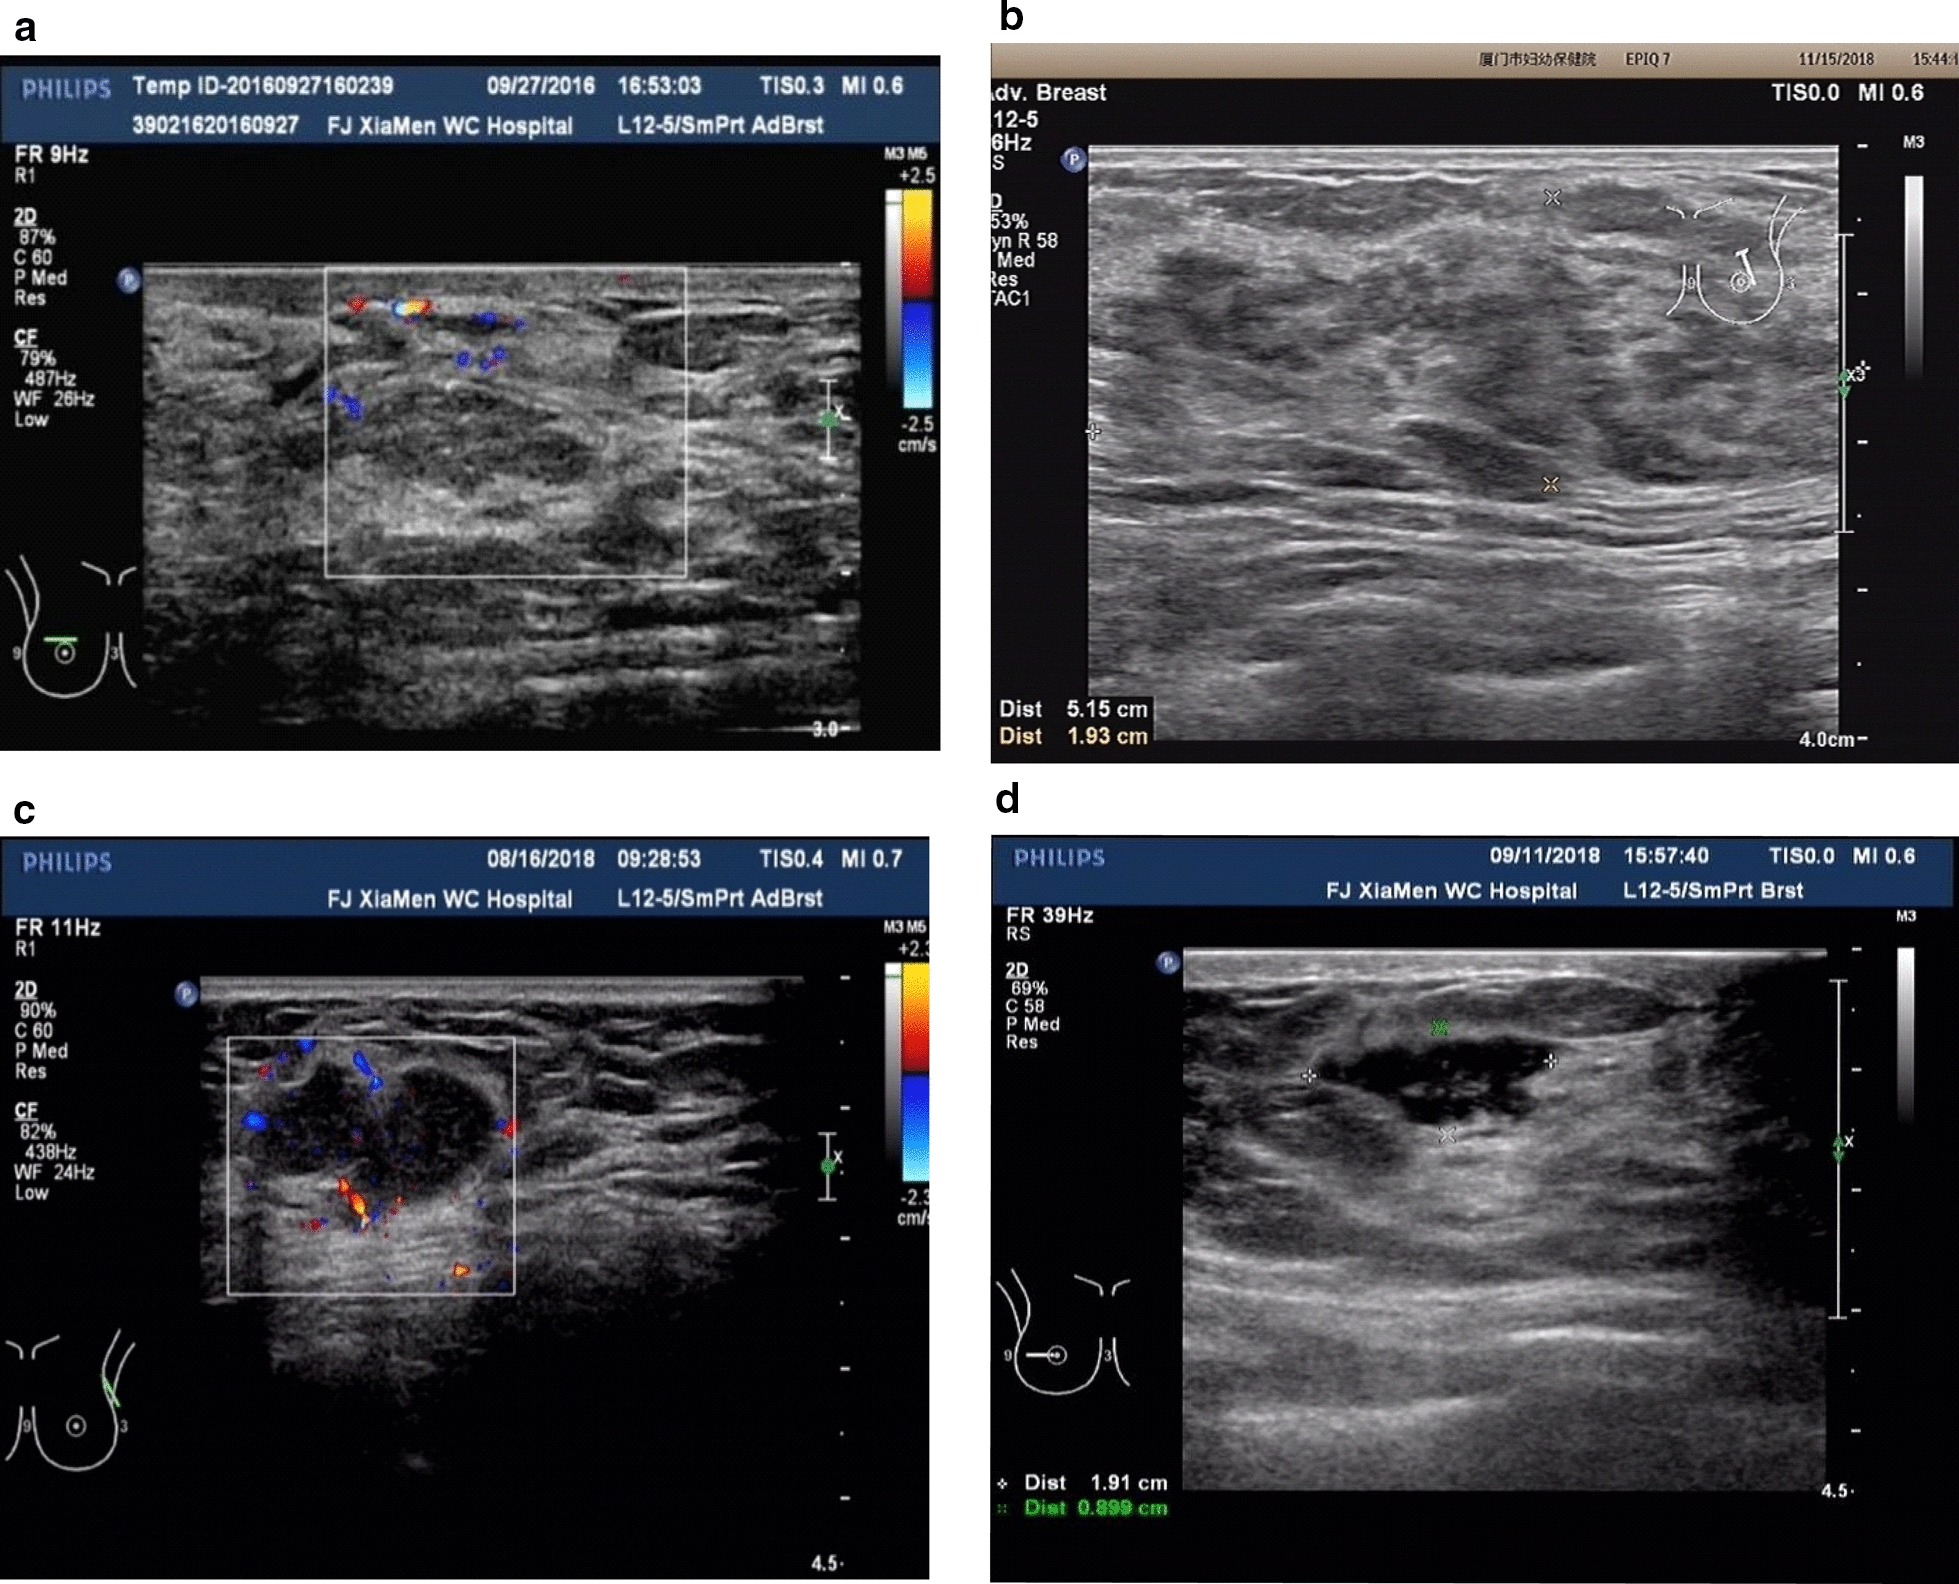

As described in the literature, ultra-sonographic findings of granulomatous lobular mastitis are nonspecific and are occasionally interpreted as malignant [3, 4]. Yaghan [2] first proposed a classification system for IGM that provides therapeutic clues and helps to predict recurrence. Referring to this classification and the combined the experience of our department, the ultrasound classification of the lesion can be categorized as: diffuse type (large patchy hypoechoic or mixed echo area scattered in the lobules; often existing across multiple quadrants without obvious borders; no display of normal glands in the lesion area, and the echo is significantly lower than that of normal glands; many low and weak abscess cavities in the glands with multiple irregular sinus tracts, which can be penetrated and can further invade the skin to form sinus tracts with rich blood supply), sheet hypoechoic type (confined in one quadrant, mainly characterized by patchy hypoechoic areas with or without abscesses inside, and with unclear borders), localized abscess type (single or multifocal abscesses with clear borders) and localized hypoechoic mass type (hypoechoic nodules with uniform or uneven internal echo, with clear borders) (Fig. 2).

Fig. 2.

Analysis of the results of ultrasound classification of lesions. a A mixed type of diffuse abscess. Large patchy hypoechoic or mixed echo areas scattered; glands and multiple abscess cavities under the skin form tunnels; b a sheet hypoechoic type. Sheet hypoechoic area showed unclear borders, disordered structure, and no abscess cavity; c a localized abscess type. There were multiple abscesses with clear borders; d a localized hypoechoic mass type. The echo was uneven and irregular, but with clear borders